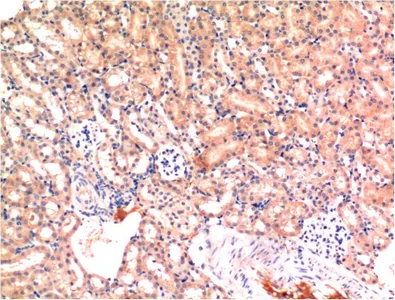

Active Caspase-3(5E1)Mouse Monoclonal Antibody

Cat: AMM06555

Size1:50μL Price1:$128

Size2:100μL Price2:$230

Size3:200μL Price3:$380

Application:IF-P,IF-F,ICC/IF,WB,IP,IHC-P

Reactivity:Human,Mouse,Rat,Chicken

Conjugate:Unconjugated

Optional conjugates: Biotin, FITC (free of charge). See other 26 conjugates.

Gene Name:CASP3